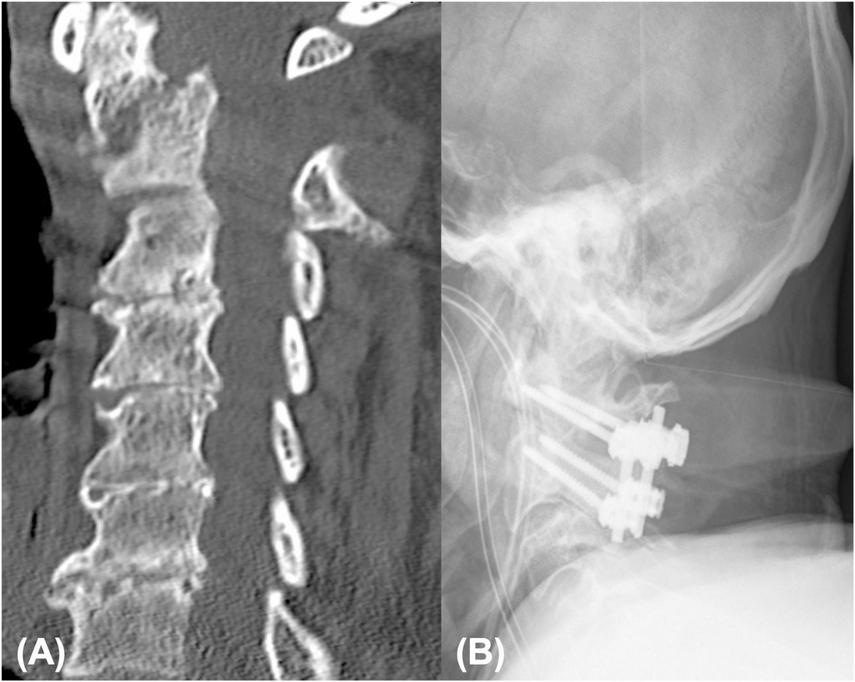

FIGURE 1

A total of 85 year male patient presenting with arm monoparesis: emergency CT showing type II odontoid fracture with anterior displacement (A), post-operative anterior-posterior radiographs displaying posterior screw fixation of C1/C2 (B).